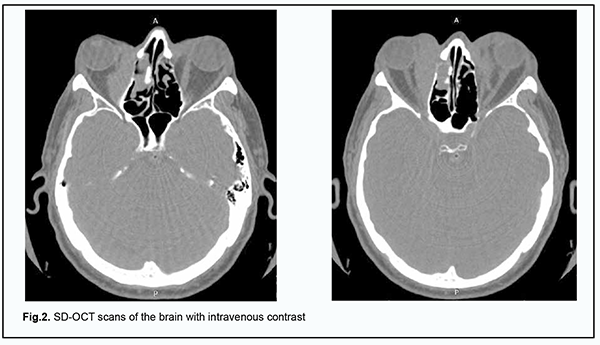

He was recommended to have a brain MRI with a focus on bilateral orbital imaging; spectral-domain optical coherence tomography (SD-OCT); and a complete blood cell (CBC) count. In addition, he was recommended to consult an endocrinologist and an oncologist. CBC results: hemoglobin (Hgb), 115 g/L; red blood cells (RBC), 4.2 х 106/mm3; white blood cells (WBC), 6.0 х 103/mm3; platelets, 2.4 х 105/mm3; percentage of bands, 3%; percentage of segmented neutrophils, 3%; percentage of eosinophils, 5%; percentage of eosinophils, 2%; percentage of lymphocytes, 25%, and RBC sedimentation rate, 17 mm/h. Blood: AB+ Rh positive. Blood biochemistry analysis: total blood protein, 74.6 g/L; urea, 6.4 mmol/L; creatinine, 88.0 µmol/L; total bilirubin, 21.6 µmol/L. Thyroid analysis: thyroid-stimulating hormone (TSH), 1.10 µU/ml; free thyroxine (FT4), 1.0 ng/div; anti-thyroid peroxidase antibodies, 0.9 U/ml. It was concluded that the patient had mild anemia and mild hyperbilirubinemia. On May 8, 2018, he underwent brain MRI at the Radiographic Imaging Department of the Vinnytsia Regional Clinical Hospital. Based on the results of MRI, the conclusion was as follows: Additional masses of unclear origin were noted in the superior and medial orbital cones. One cannot exclude changes in the muscles in the presence of changes in the thyroid gland and inflammation. It is likely that the neoplasms are in the presence of fibromatosis. Figure 2A, B shows SD-OCT scans of the brain with intravenous contrast.

Biopsy was taken from the upper eyelid neoplasms by the oncologist in accordance with MRI-based and SD-OCT-based conclusions. Biopsy analysis demonstrated that the tumor cell morphology and the expression of antibodies by tumor cells corresponded to an extranodal B-cell lymphoma of the marginal zone (MALT lymphoma). Because of biopsy results, on May 29, 2018, the patient was hospitalized at the Podillia Regional Oncology Center with a preliminary diagnosis of orbital lymphoma. On January 1, 2019, computed tomography of the brain, chest and abdomen with intravenous contrast was performed, demonstrating reduced pneumatization of the left frontal sinus with a contrasted soft tissue component at the level of paranasal sinuses; apneumatosis of the right medial ethmoid labyrinth; and fluid with small air inclusions at the level of the right maxillary sinus. In addition, CT demonstrated a 32 x 14 mm elongated soft-tissue mass in the right medial orbit displacing the medial rectus laterally and a similar 25 x 13 mm mass in the left proximal orbit. It was concluded that there was CT evidence of a right maxillary sinusitis, ethmoiditis, focal changes in the left frontal sinus, orbits, lungs, and posterior mediastinum, likely as manifestations of the primary disease, a non-Hodgkin's lymphoma. On April 2, 2019, computed tomography of the brain and abdomen without intravenous contrast was performed, and it was concluded that there was no CT evidence of focal volume changes in the brain, but there was CT evidence of polysinusitis progression and regression of focal changes in the orbit and lungs. The patient was consulted by a department therapist. Therapist's opinion: coronary artery disease (atherosclerotic cardiosclerosis, heart failure 0 level), chronic pancreatitis in unstable remission, and osteochondrosis of the cervical spine. On June 15, 2019, multislice spiral computed tomography (MSCT) of the chest and abdomen with intravenous contrast was performed, demonstrating signs of secondary lesions of the lungs, pleura and lymph nodes of the mediastinum. The patient underwent inpatient surgery for removal of a soft tissue tumor of the right upper eyelid. Gross specimen description: The tumor, 2.0 cm in diameter, was round, hard and knobbly. The tumor when excised showed a thin wall and homogeneous structure, was pale pink and hard at touch. Histopathological conclusion: The tumor exhibited morphological findings and the pattern of antibody expression strongly suggestive of extranodal, non-Hodgkin’s B-cell lymphoma of the marginal zone (MALT lymphoma). Given the results of primary and adjunct methods of examination, a final diagnosis of “extranodal, non-Hodgkin’s B-cell lymphoma of the marginal zone (MALT lymphoma) of stage 3a, with stage 3 metastases in the lungs, pleura and lymph nodes of the mediastinum” was established. The secondary diagnosis was coronary artery disease (atherosclerotic cardiosclerosis, heart failure 0 level), chronic pancreatitis in unstable remission, and osteochondrosis of the cervical spine. A decision was made to administer a course of polychemotherapy. On March 11, 2019, the patient was re-admitted to the Podillia Regional Oncology Center (radiotherapy) for in-patient treatment with a diagnosis of “non-Hodgkin’s B-cell lymphoma of stage 3 and Clinical Group 3; coronary artery disease (atherosclerotic cardiosclerosis, heart failure 0 level) and chronic pancreatitis in remission”. He received brain radiotherapy (32 Gy) and 8 courses of polychemotherapy, and was discharged with recommendations for rehabilitation. The patient was followed up at the local otolaryngologist’s office and at the oncologist’s office at the Podillia Regional Oncology Center, Vinnytsia, and was recommended to have CT of the paranasal sinuses. Repeat CT of the paranasal sinuses performed on August 9, 2019, showed mild improvement (a reduced soft-tissue component at the level of the paranasal sinuses). In addition, the CT examination revealed no change in the bone defects of the medial wall of the right orbit. No visible pathological changes in the brain were observed. The patient was observed by the ophthalmologist throughout the course of treatment and attended follow-up appointments. He is stabilized at present with regard to ocular symptoms, has no ocular complaints. In addition, visible regression of eyelid tumors and exophthalmos is observed, and the position of the eyes is almost correct. At the moment, the patient is under observation by an oncologist and on the way to stabilization of his major disease. Discussion Management of orbital non-Hodgkin’s lymphomas remains a challenge requiring a multidisciplinary approach involving ophthalmologists and oncologists. The ophthalmologist is to detect the orbital neoplasm early and to perform its diagnostic evaluation, and the oncologist collects the material for morphological and immunohistochemical analysis. Patients with this pathology should be monitored by the ophthalmologist throughout the course of treatment to assess treatment effect. Such patients require lifetime monitoring to identify and prevent recurrence. Close cooperation of the ophthalmologist and the oncologist is important in the diagnostic evaluation of orbital tumor disorders and is a prerequisite for treatment success.